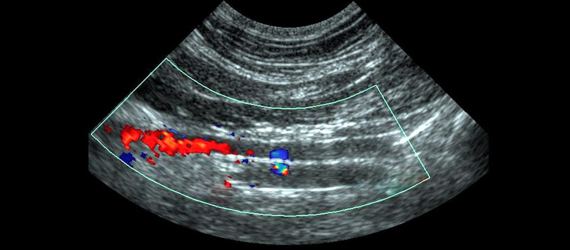

Ecografía Renal

Es la encargada de utilizar ondas sonoras para producir imágenes de las estructuras del riñón.